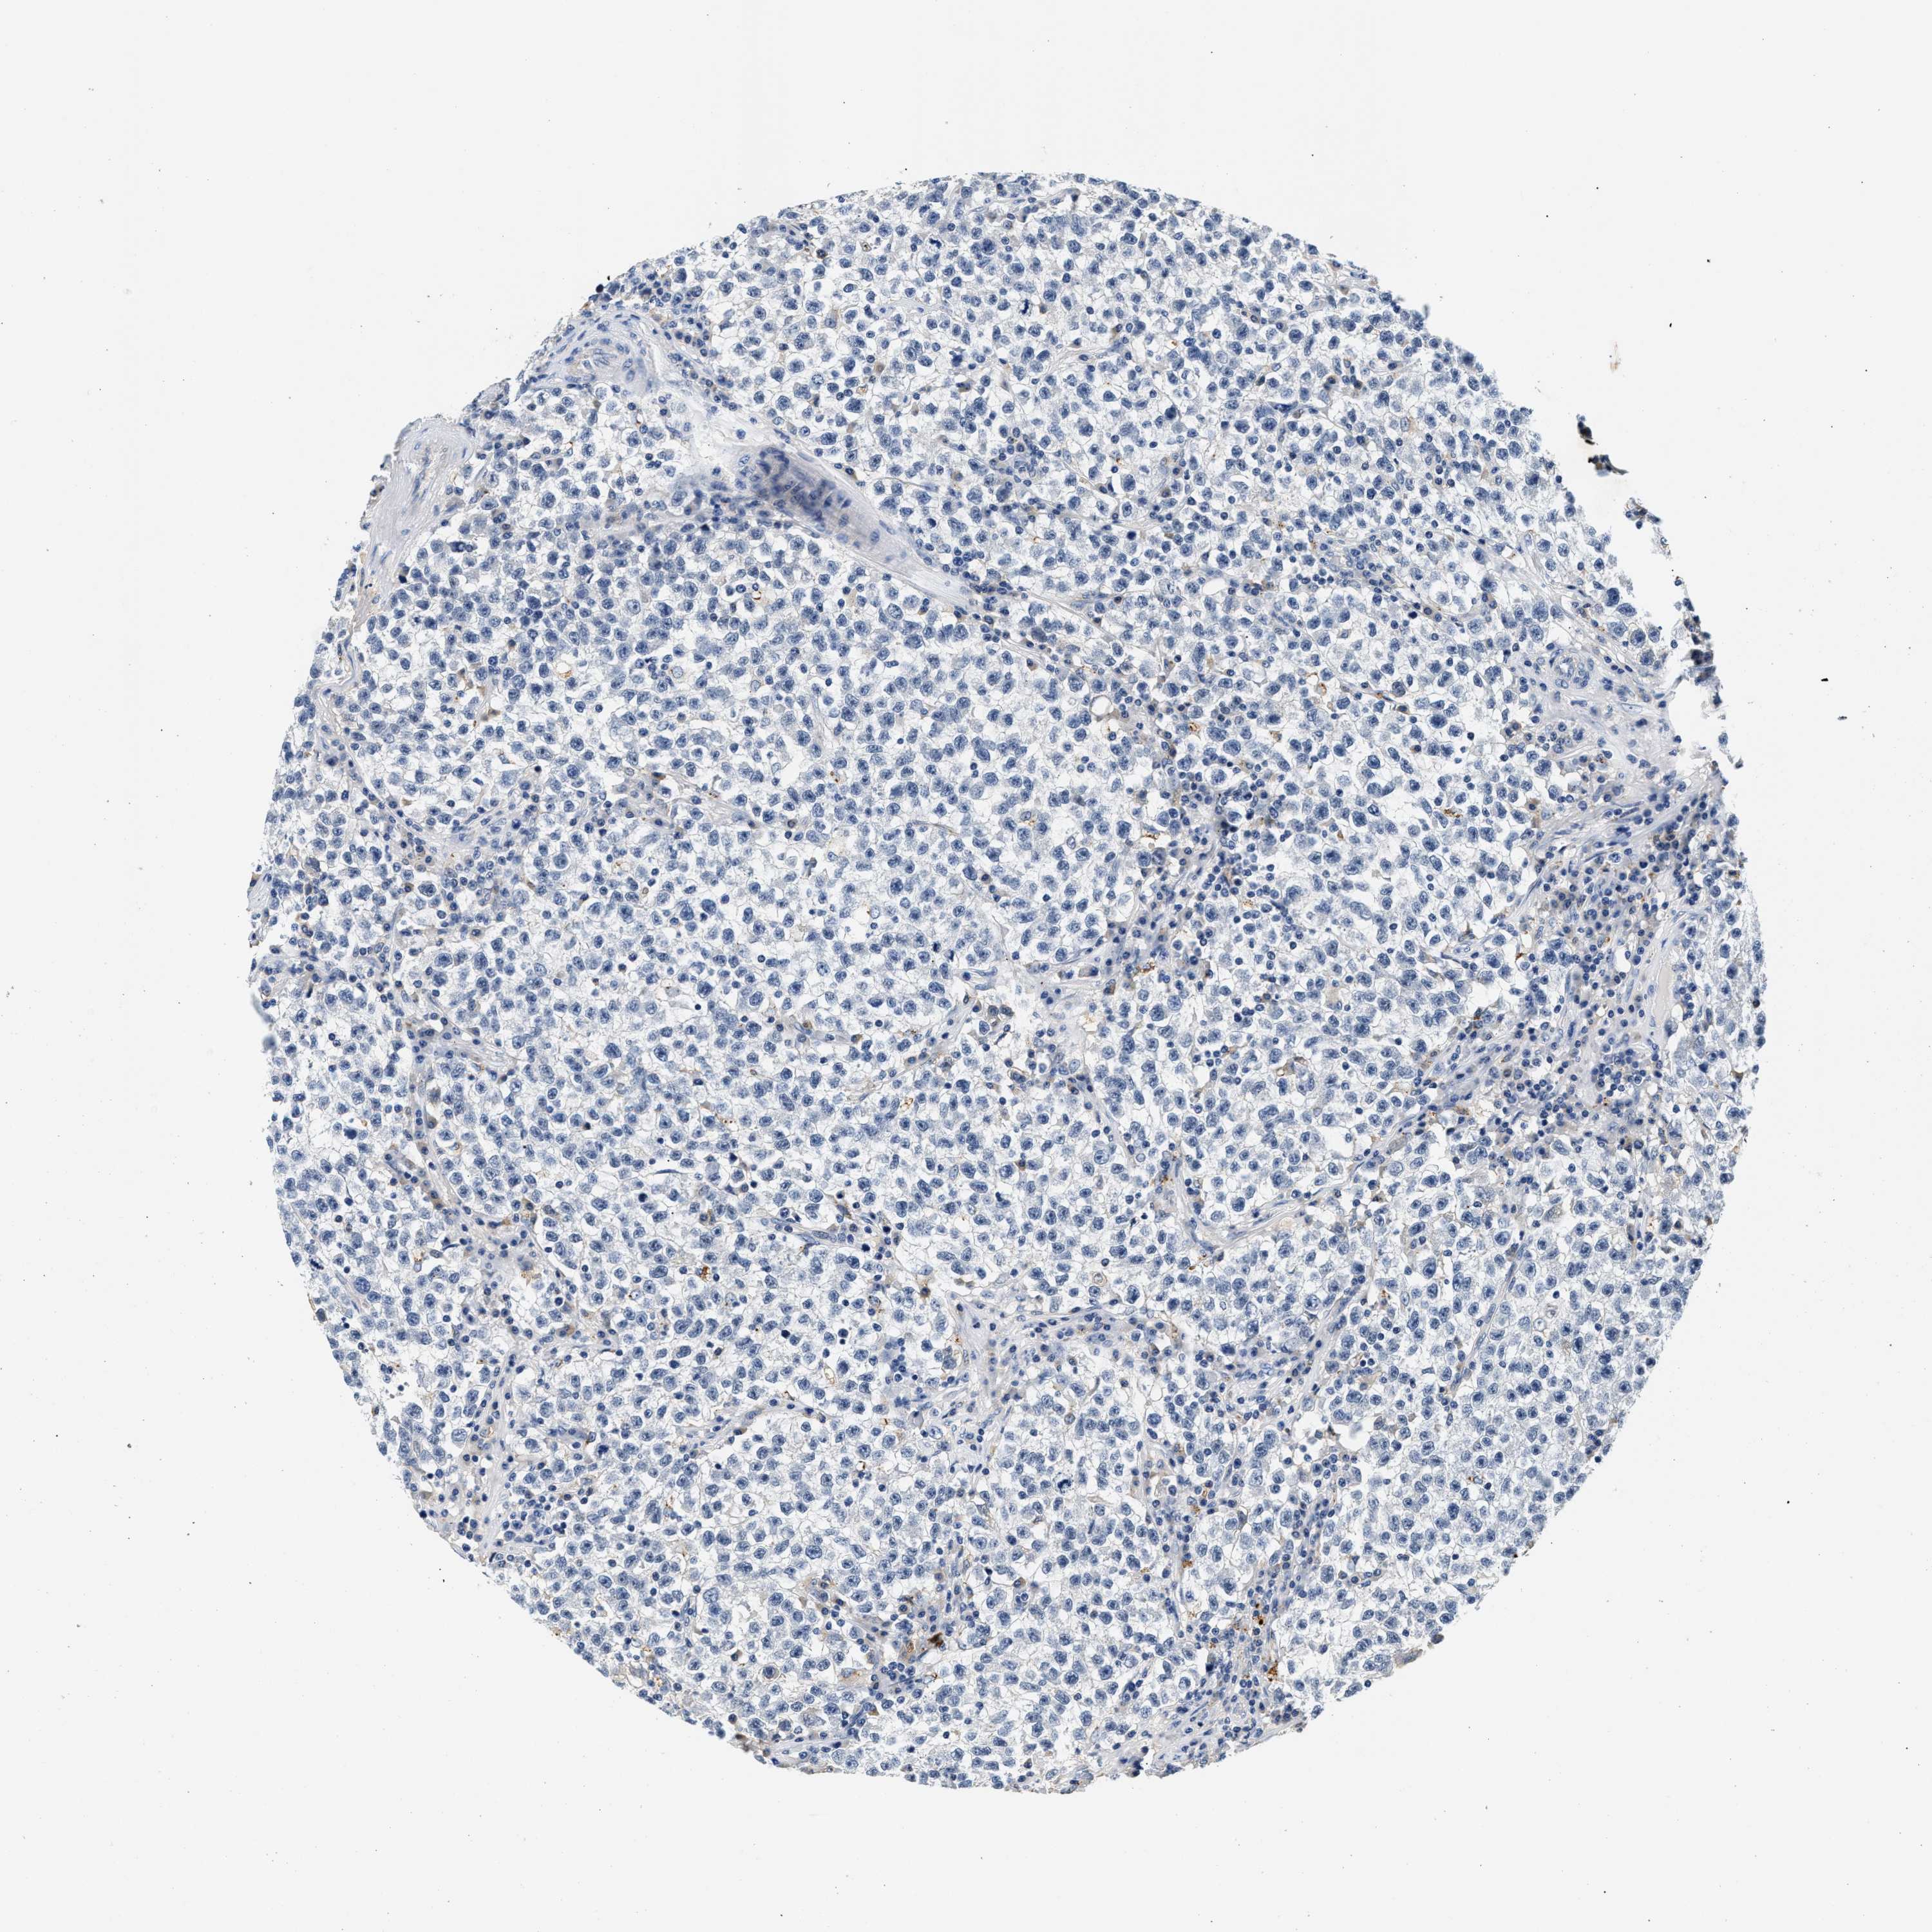

TESTIS CANCER - Protein expressioni

A mouse-over function shows sample information and annotation data. Click on an image to view it in a full screen mode. Samples can be filtered based on level of antibody staining by selecting one or several of the following categories: high, medium, low and not detected. The assay and annotation is described here.

Note that samples used for immunohistochemistry by the Human Protein Atlas do not correspond to samples in the TCGA dataset.

Antibody stainingi

Antibody staining in the annotated cell types in the current human tissue is reported as not detected, low, medium, or high, based on conventional immunohistochemistry profiling in selected tissues. This score is based on the combination of the staining intensity and fraction of stained cells.

Each image is clickable and will lead to virtual microscopy that enables deeper exploration of all samples and also displays staining intensity scores, fraction scores and subcellular localization as well as patient and tissue information for each sample.

Antibody HPA020391

Staining

High

Medium

Low

Not detected

Intensity

Strong

Moderate

Weak

Negative

Quantity

>75%

75%-25%

<25%

None

Location

Nuclear

Cytoplasmic/membranous

Cytoplasmic/membranous,nuclear

Carcinoma, Embryonal, NOS

Seminoma, NOS